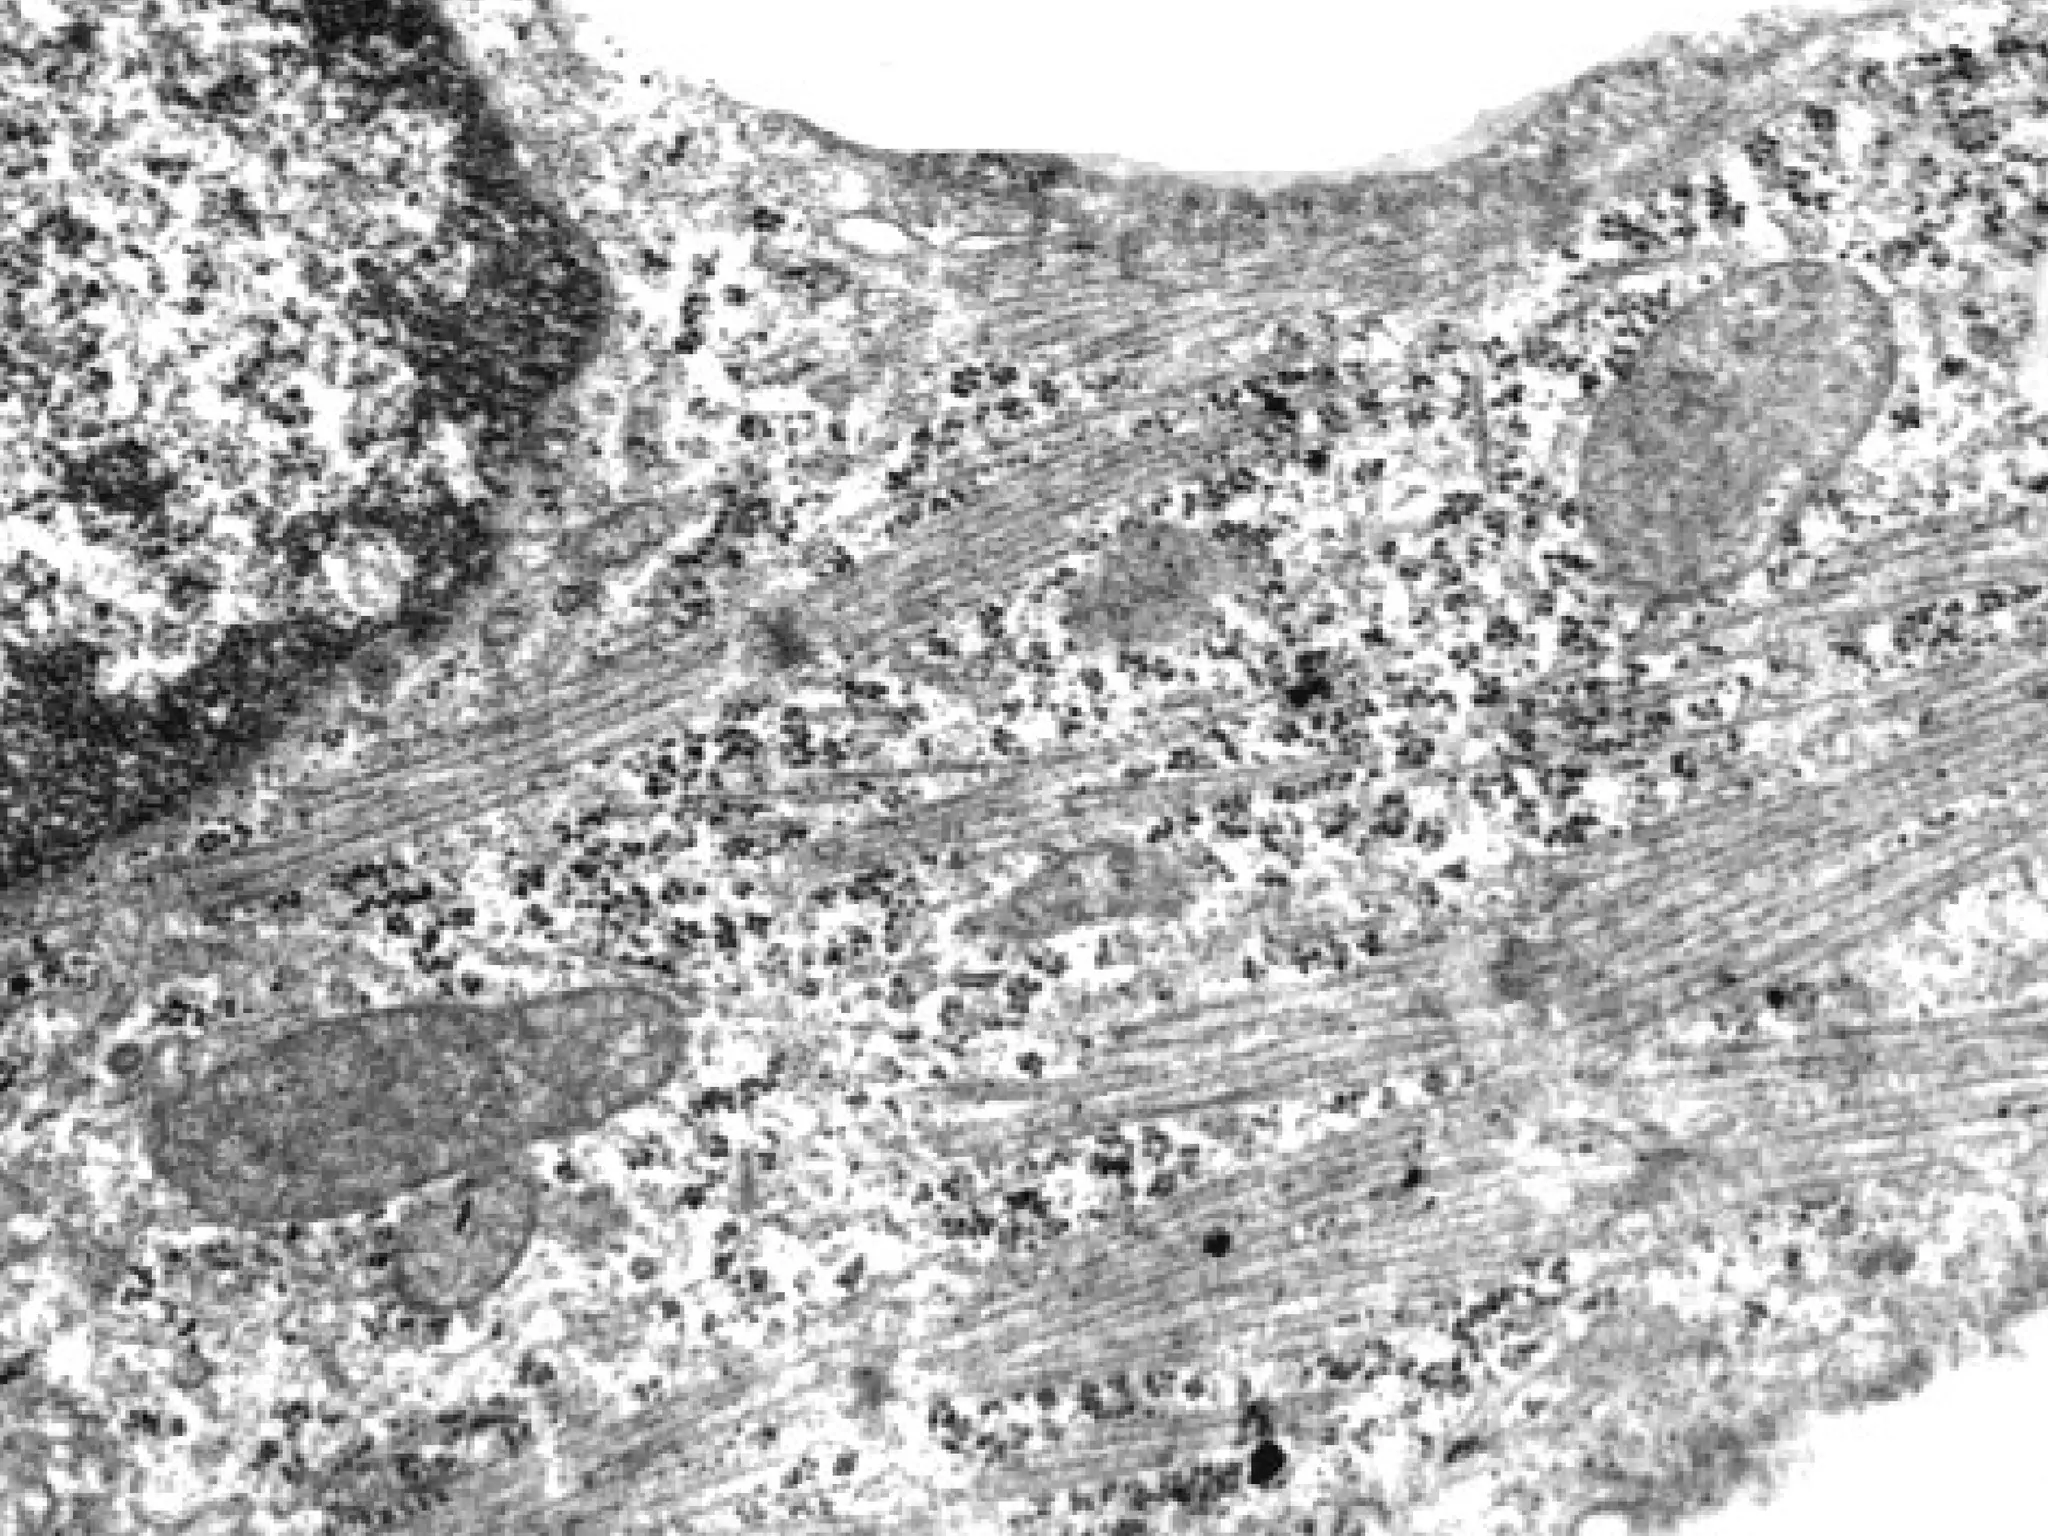

НЕОНАТАЛЬНИЙ КАРДІОМІОЦИТ ЩУРА

ПІСЛЯ 24 ГОДИН КУЛЬТИВУВАННЯ

МОРФОЛОГІЧНІ

ПРОЯВИ АПОПТОЗУ:

фрагментація ДНК,

каріорексис, каріолізис,

конденсація мітохондрій,

утворення апоптотичних

тілець та ін.